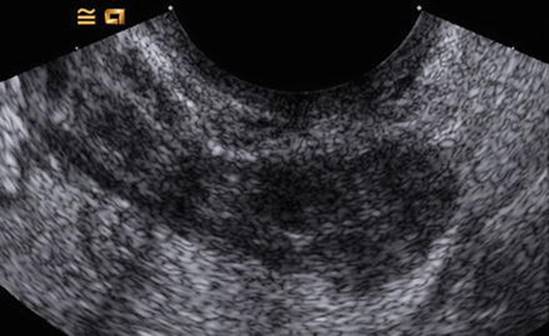

Fig. 6.1

Acute salpingitis by ultrasound, verified by laparoscopy. The sausage-shaped solid structure corresponds to the inflamed tube (Reprinted from Romosan et al. [27], by permission of Oxford University Press and The European Society of Human Reproduction and Embryology)